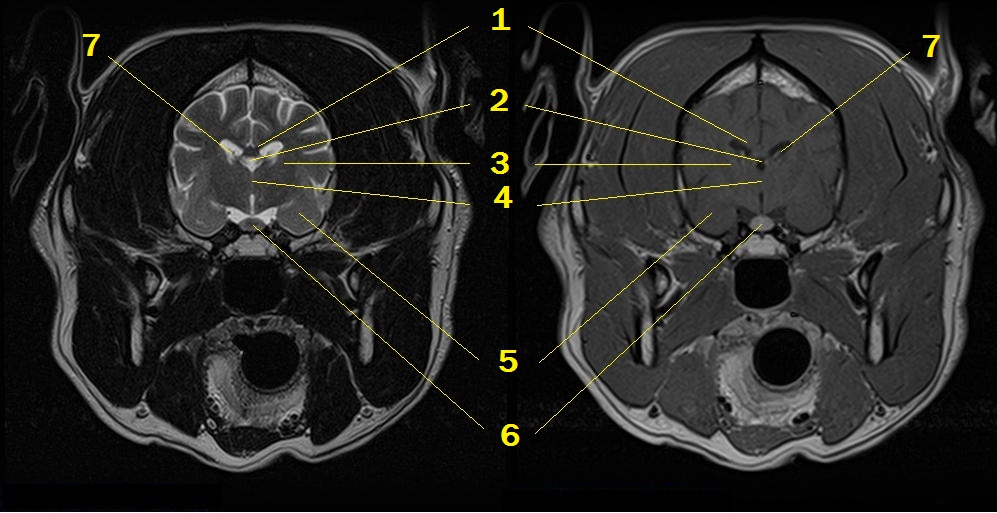

MRI anatomy 5

Q. Identify the structures labeled below:

A.

1. corpus callosum

2. third ventricle

3. thalamocortical fibers

4. interthalamic adhesion

5. amygdaloid body in the piriform lobe

6. pituitary gland

7. choroid plexus in the lateral ventricle